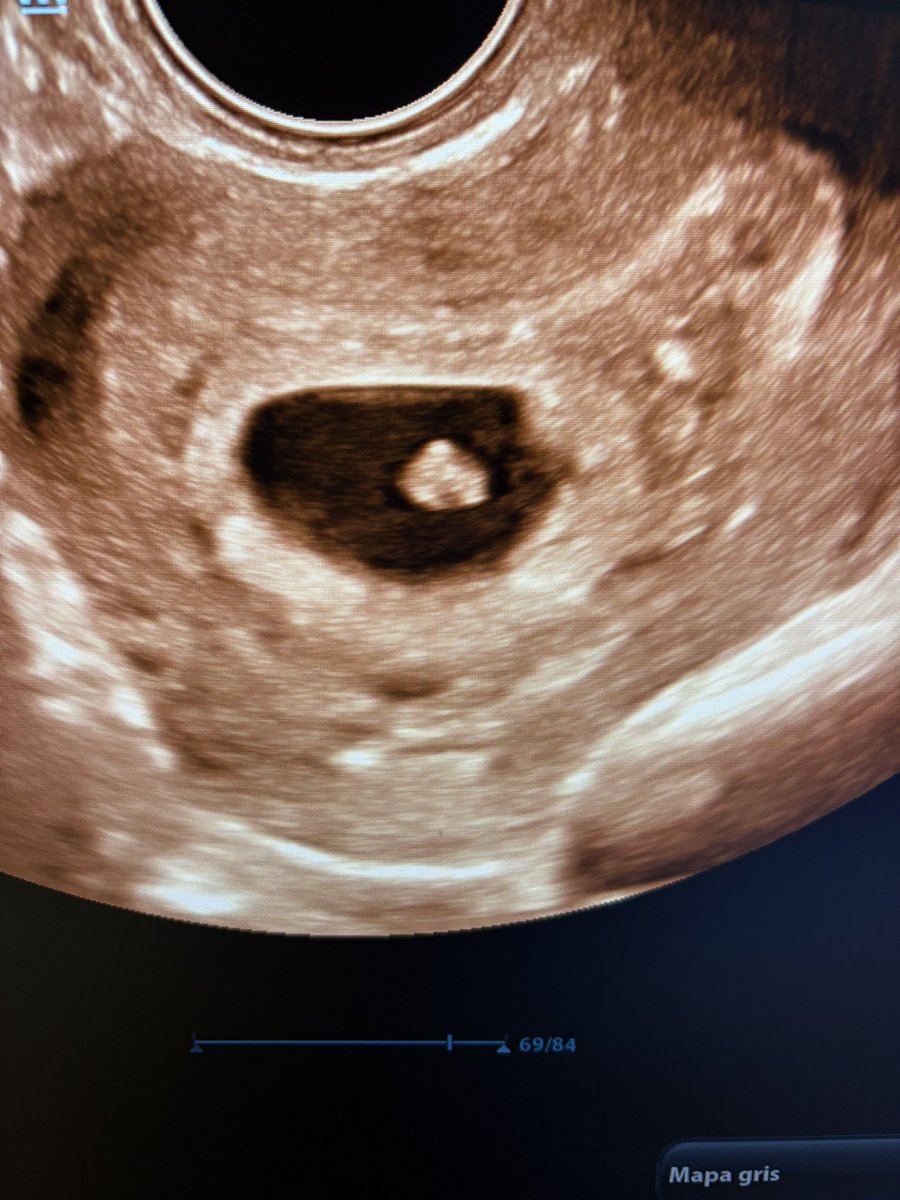

“Llevo 5 años sin contracepción; yo medía todos los años la hormona antimulleriana y estaba bajita. Cada vez bajaba más, y el último control estaba en 0,37”. Acá está el 0,37 con latido 💗. Para una mujer de 39 años, sin hijos, es una noticia que cambia la vida, para bien.

Acá está el 0,37 con latido 💗.

Para una mujer de 39 años, sin hijos, es una noticia que cambia la vida, para bien.